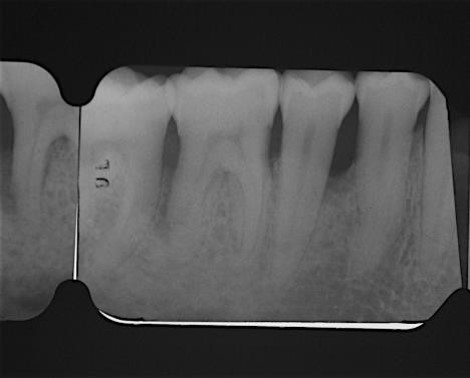

Radiographic view before periodontal regenerative therapy with Straumann® Emdogain®. A deep intrabony defect appeared mesially and distally on the left mandibular first premolar. Pre-surgical probing measured 8 mm. The defect morphology presented as well-contained.